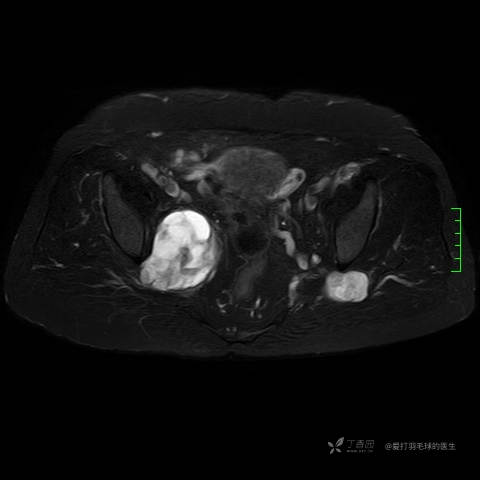

主诉:患者因反复右侧腰痛伴右下肢麻木2年余入院。

简要病史:自诉右甲状腺功能亢进症多年,规律服药,平素多有心悸、胸闷、活动后明显。既往腰椎椎管内肿瘤切除术。